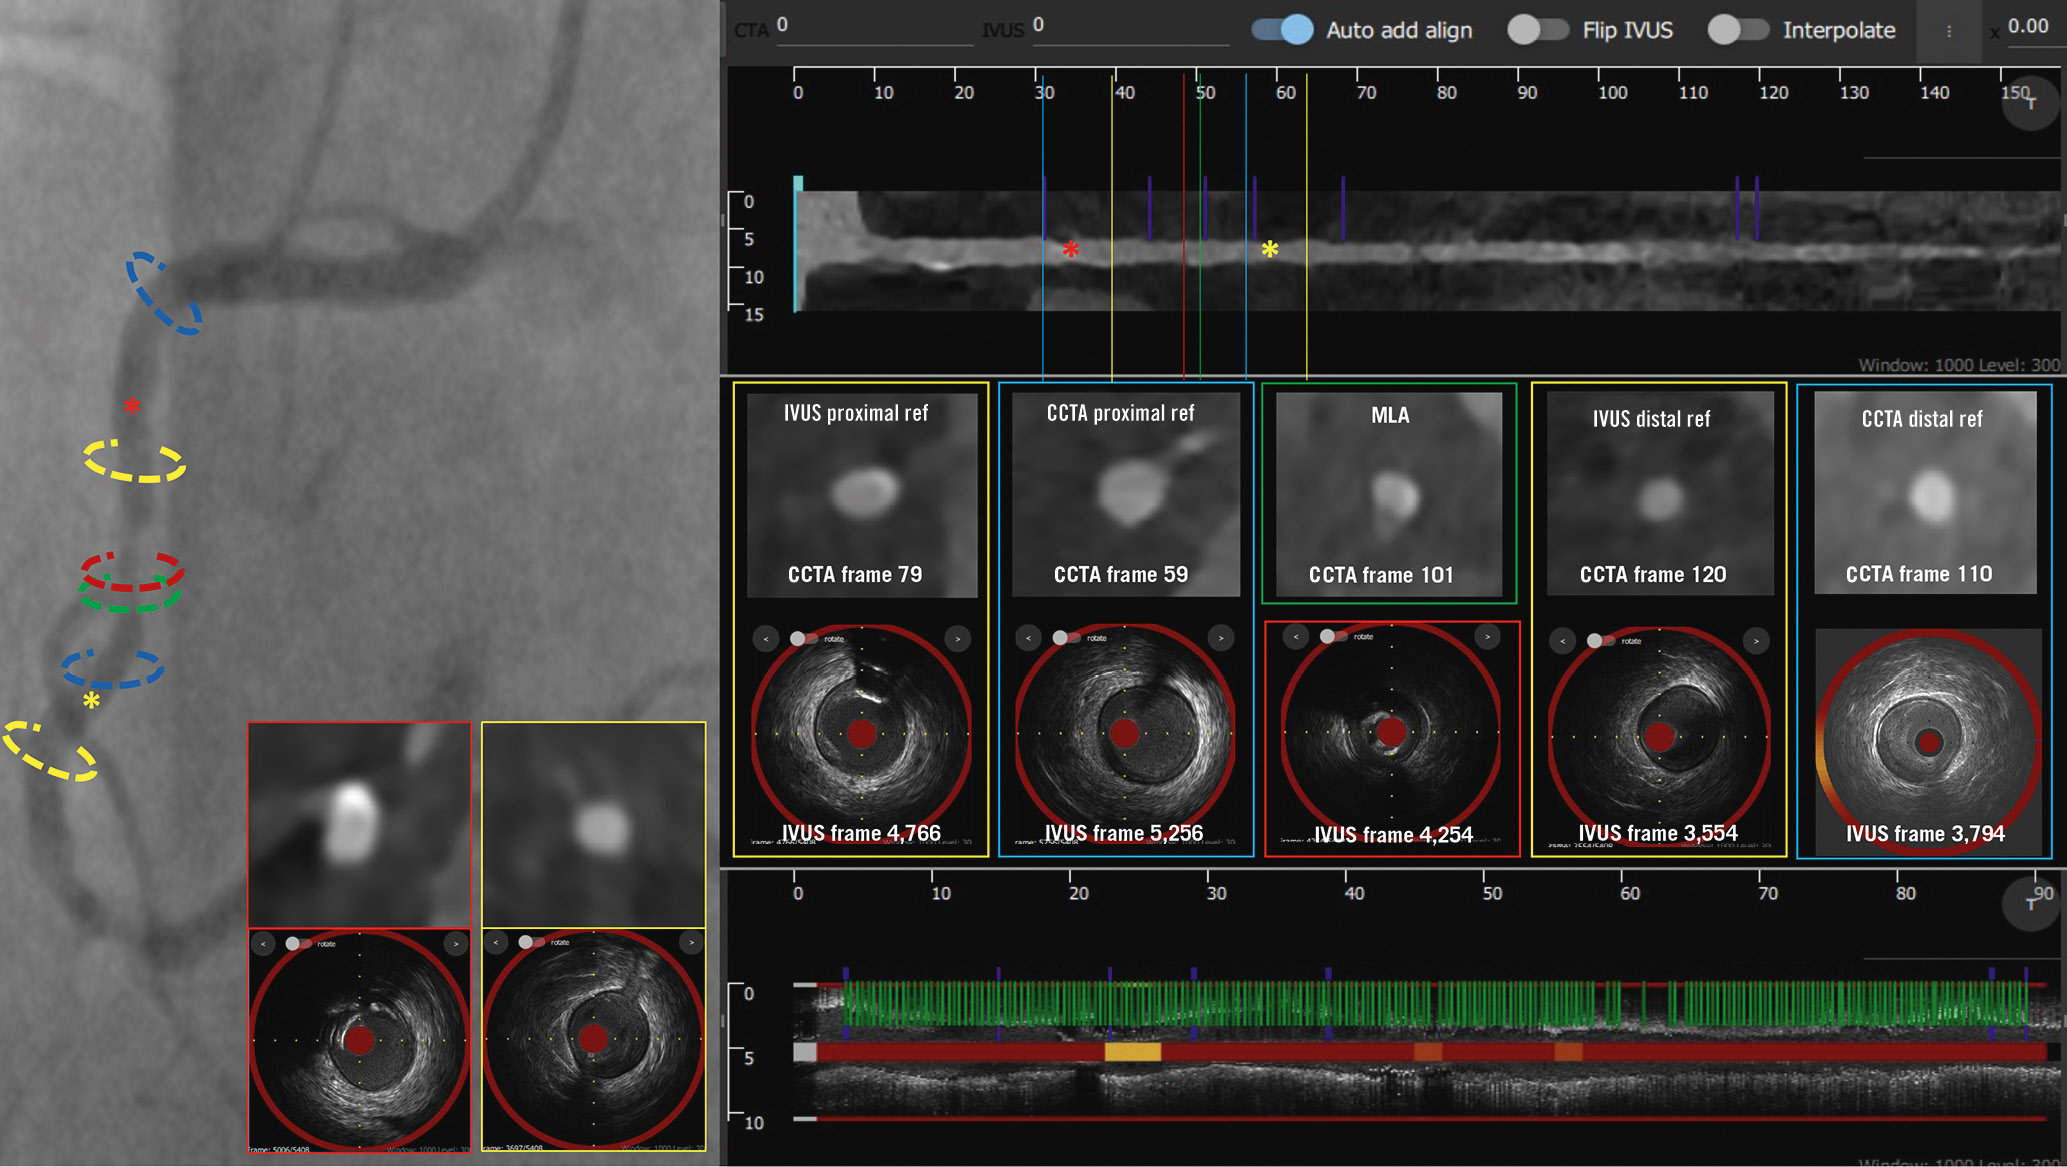

In total, 186 vessels were included in the final analysis. The mean length of the studied segments was 76.9±27.4 mm. An example of matched CCTA and NIRS-IVUS spread-out plots are shown in Figure 1. The ICC and the Pearson correlation coefficient were high for the lumen volume, vessel volume and TAV, moderate for the PAV and CaBI, and weak for the LCBI and maxLCBI4mm (Table 1). CCTA underestimated the lumen and vessel volumes, TAV and PAV, and overestimated the LCBI, but there was no difference between the two modalities for the CaBI or maxLCBI4mm (Figure 2). However, the LoA were wide for these latter two metrics (Figure 3).

Figure 1. Lumen, vessel wall and spread-out plaque composition analysis of the NIRS-IVUS and CCTA images. A) portrays a longitudinal segment of interest in a left anterior descending artery on NIRS-IVUS, while (B) portrays the corresponding segment of interest on CCTA. The spread-out plots displaying lipid and calcific tissue distribution are also displayed. The TAV, PAV, LCBI, CaBI and maxLCBI4mm estimations of both modalities are shown at the bottom. The cross-sections showing the MLA with the annotated lumen and vessel wall borders and the circumferential distribution of tissue types on NIRS-IVUS and CCTA are portrayed in the images on the right in (A) and (B). CaBI: calcific burden index; CCTA: coronary computed tomography angiography; LCBI: lipid core burden index; maxLCBI4mm: maximum LCBI in a 4 mm segment; MLA: minimum lumen area; NIRS-IVUS: near-infrared spectroscopy-intravascular ultrasound; PAV: percentage atheroma volume; PB: plaque burden; TAV: total atheroma volume

The location of the minimum lumen area (MLA) and the proximal and distal landing zones on NIRS-IVUS and CCTA in the 58 vessels treated with PCI are shown in Supplementary Figure 2. In 17 lesions, the difference in the distance of the proximal or distal landing zone between NIRS-IVUS and CCTA estimations was >5 mm; in 11 cases, CCTA indicated implantation of significantly longer stents, and in 8 cases, it indicated significantly shorter stents compared to NIRS-IVUS. The overestimation of the stent length with CCTA was mainly attributed to the presence of calcific plaques near the reference segment, resulting in an overestimation of the PB in these locations due to the blooming artefacts. Conversely, CCTA failed to detect fibrotic plaques seen on NIRS-IVUS, resulting in an underestimation of the stent length in fibrotic lesions with diffuse disease (Figure 4).

Figure 4. Case example of NIRS-IVUS- and CCTA-guided right coronary artery PCI. The treated lesion is shown on the coronary angiogram, along with CCTA and NIRS-IVUS longitudinal images. The location of the MLA on NIRS-IVUS (red) and CCTA (green) are different. The NIRS-IVUS proximal and distal reference areas are marked in yellow, while the CCTA proximal and distal reference areas are marked in blue. There was a significant difference in the landing zone estimations between NIRS-IVUS and CCTA; CCTA overestimated the PB in the calcific segment proximal to the lesion, while distally it missed a fibrotic plaque compared to NIRS-IVUS. CaBI: calcific burden index; CCTA: coronary computed tomography angiography; IVUS: intravascular ultrasound; MLA: minimum lumen area; NIRS-IVUS: near-infrared spectroscopy-intravascular ultrasound; PB: plaque burden; PCI: percutaneous coronary intervention